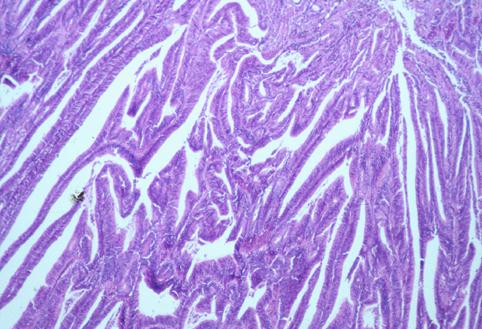

질환(병리주체)의 분류 악성 상피성종양/선암

부위(장기별) 대장/충수

검사방법 마이크로

종양의 육안분류 2형(궤양국한형)/

종양의 최대경(밀리미터) 25~29

종양의 심달도 s(a)